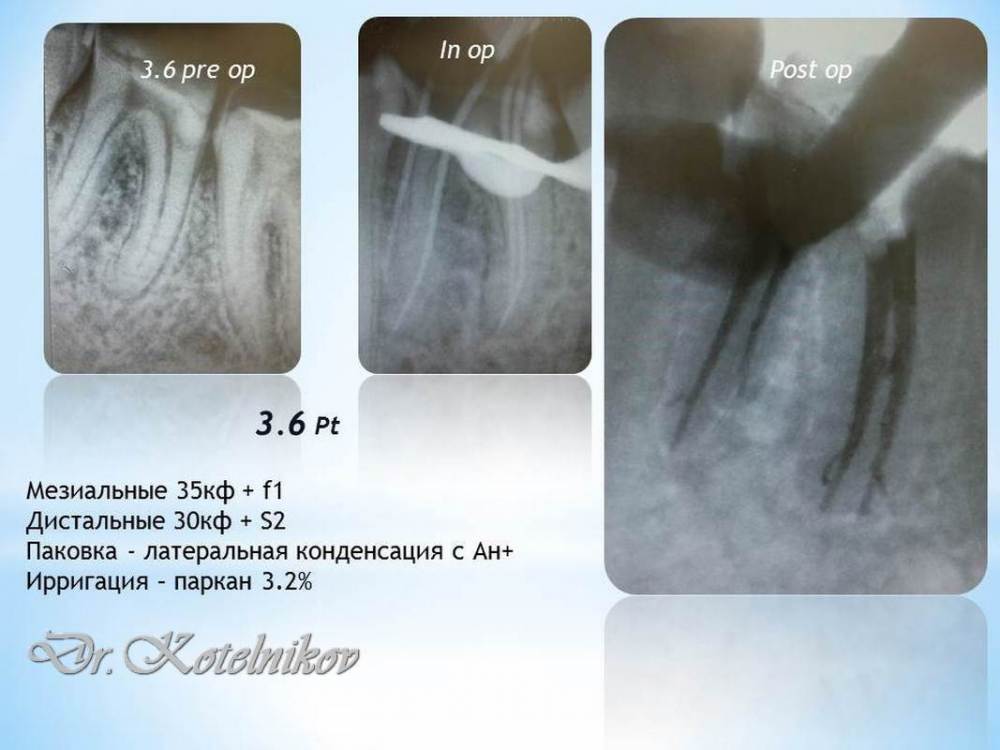

Ico Опубликовано 20 февраля, 2022 Автор Поделиться Опубликовано 20 февраля, 2022 Из старого,возможно уже постил где-то тут)Считаю такую работу оправданной,пациент 20 лет с мостом проходил,с новым уже лет 5 ходит. 3 Ссылка на комментарий

Ico Опубликовано 21 февраля, 2022 Автор Поделиться Опубликовано 21 февраля, 2022 (изменено) 1 час назад, Карен Аванесов сказал: как верхние нагрузят имплы и 3.6 к тебе тоже придет) 36 тоже перелечил тогда еще,но там все стандартно было этому кейсу 5 лет,пересмотрел даты. Изменено 21 февраля, 2022 пользователем Ico Ссылка на комментарий